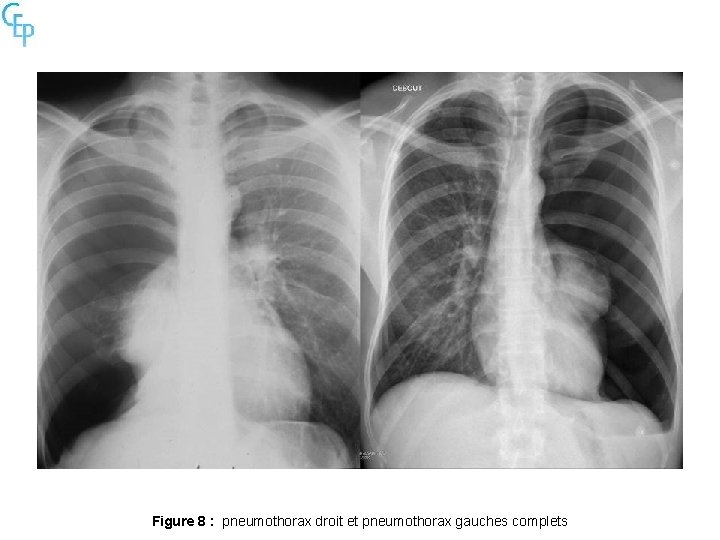

Figure 8 : pneumothorax droit et pneumothorax gauches complets